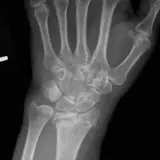

Over 2,100 interactive radiology cases, curated by radiologists for your level of training. Scroll, window, and view cases full screen — just like on PACS. Click linked findings in each writeup to jump straight to them on the image. Cases include sample reports, a focused discussion section, original illustrations, and videos.

完全交互式病例,配备您在 PACS 上期待的各项工具——滚动、调窗、缩放、平移、测量、ROI 和全屏模式。

丰富的标注直接在病例图像上突出关键发现。点击病例讲解中的关联发现,即可跳转至其在扫描上的精确位置。